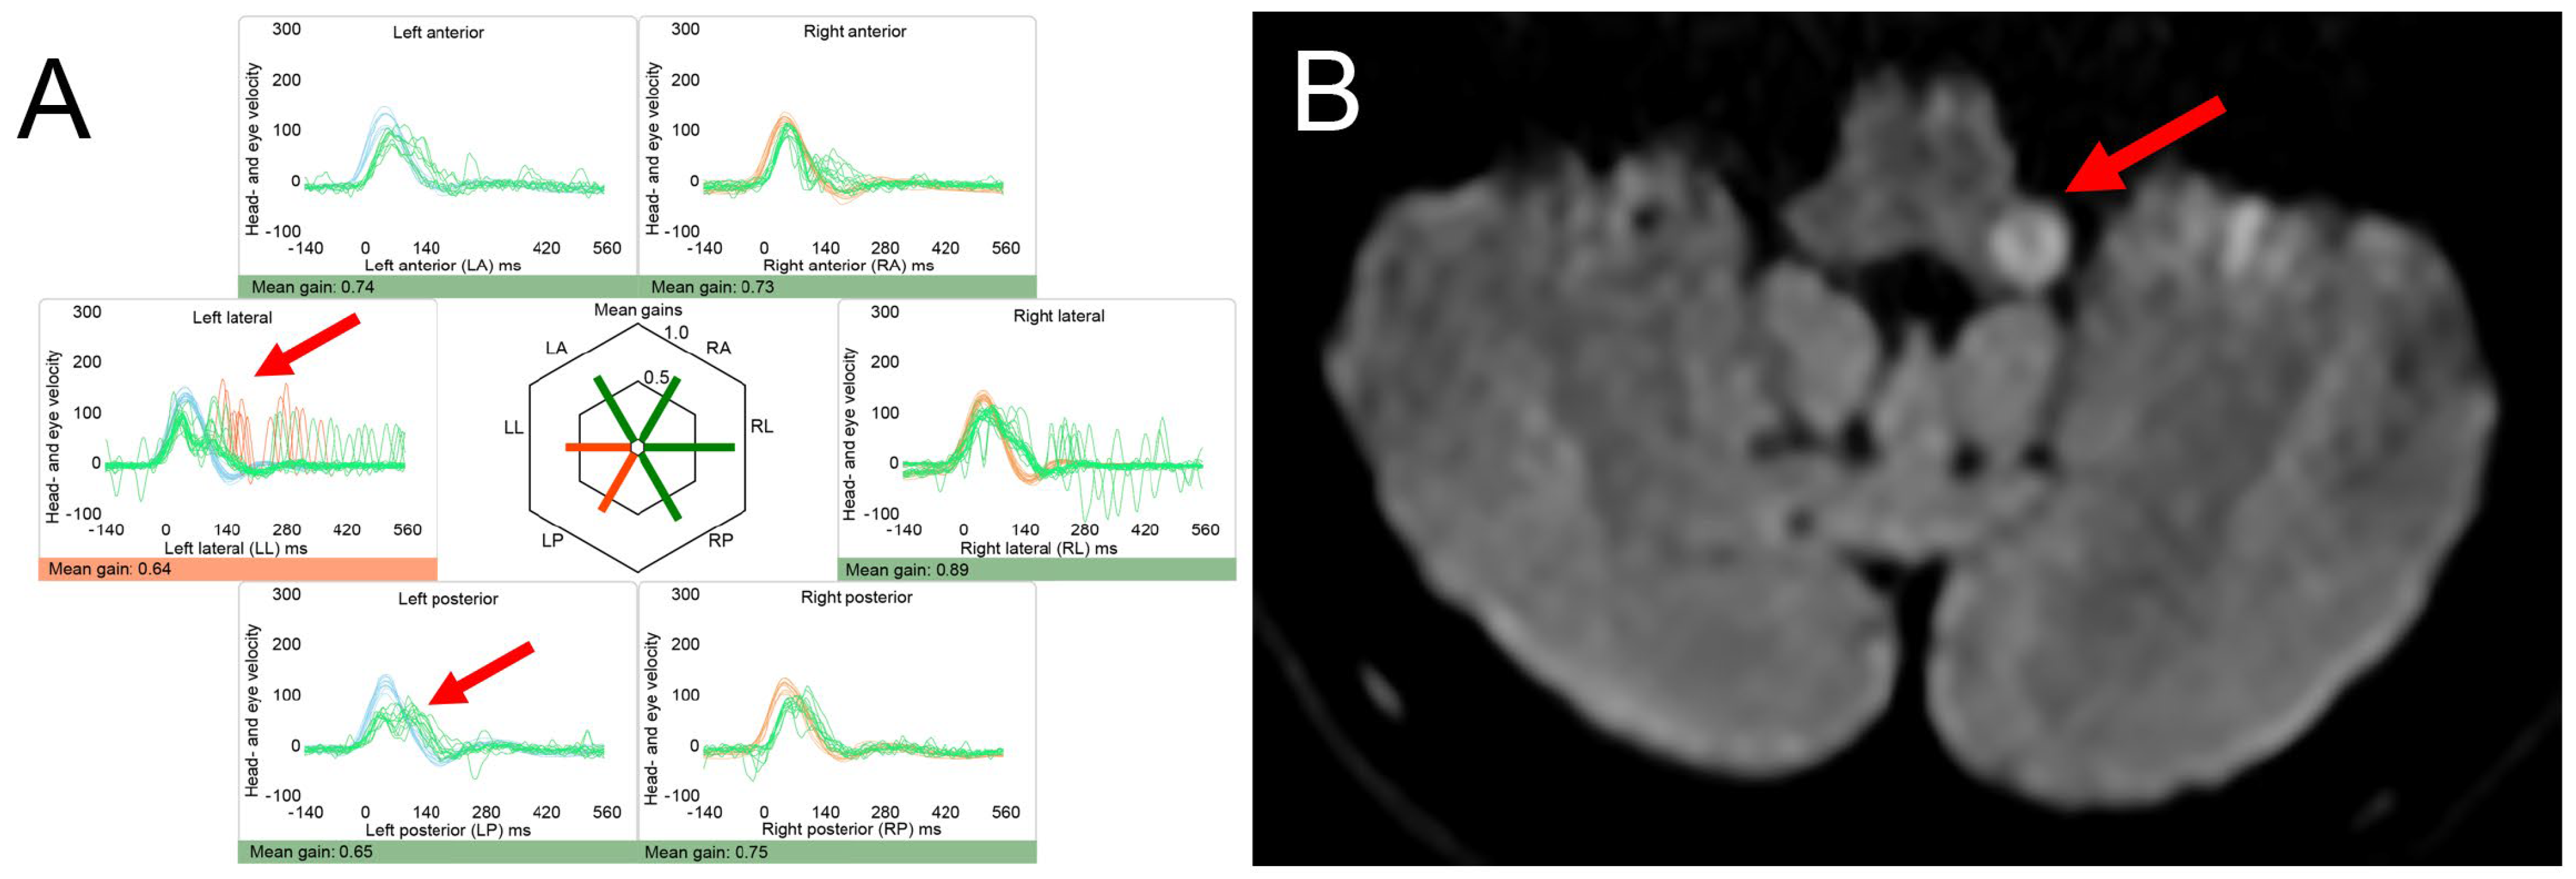

- Tarnutzer, A.A.; Bockisch, C.J.; Buffone, E.; Weiler, S.; Bachmann, L.M.; Weber, K.P. Disease-specific sparing of the anterior semicircular canals in bilateral vestibulopathy. Clin. Neurophysiol. 2016, 127, 2791–2801. [Google Scholar] [CrossRef] [PubMed]